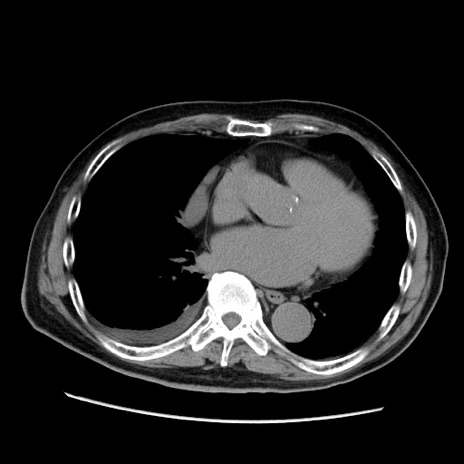

症例21(横断像)

【症例】70歳代男性

【主訴】腹痛

【現病歴】肝硬変・肝細胞癌にてかかりつけの方。約9時間前に食後より腹痛出現。症状が徐々に増悪し、嘔吐出現したため来院。

【既往歴】肝硬変、肝細胞癌(RFA、TACE後)

【身体所見】意識清明、表情苦悶様、BT 36℃、BP 129/78mmHg、P 88bpm、SpO2 97%(RA)、右上腹部から心窩部にかけて圧痛あり、反跳痛なし、筋性防御あり。

【データ】WBC 5800、CRP 0.16